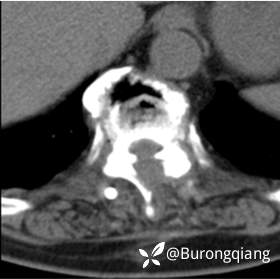

临床诊断:胸椎管狭窄

治疗经过:给予脊柱内镜下椎管扩大减压手术治疗。

治疗结果:术后两天患者可搀扶下站立,术后十天可助行器辅助行走。